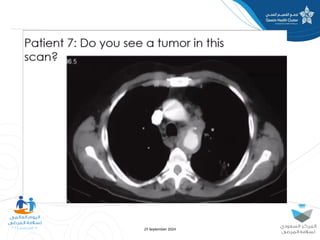

The document discusses diagnostic errors, particularly focusing on cognitive biases and their impact on decision-making in healthcare. Dr. Asmaa Fayez emphasizes the importance of recognizing and mitigating these biases to avoid human errors that can lead to serious incidents. The presentation highlights the urgent need for timely interventions in the context of patient safety.